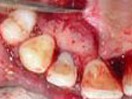

Root and Crown Fragments

are splinted with Glass

Fibre Post. Resin Cement and

Light Cure Composite

are used for this purpose.

Tooth with Fracture Extending Sub-Gingivally

Finished palatal view

of the tooth. Stitches can be seen.

Finished Labial view

Stitches can be seen.